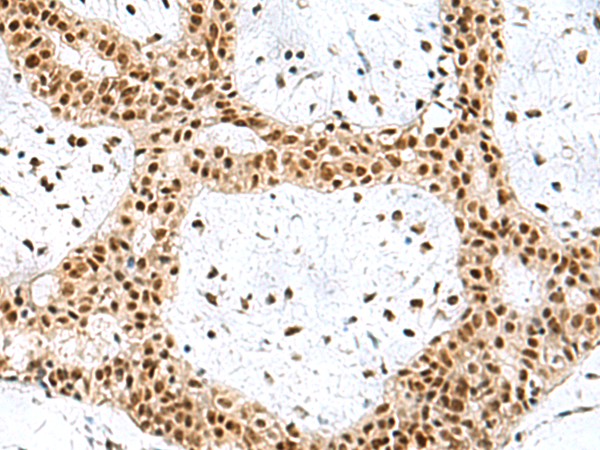

分类: 科研抗体货号: P03162别名: XE7; 721P; XE7Y; CCDC133; CXYorf3; PRKA17A; SFRS17A; AKAP-17A; DXYS155E应用: IHC反应种属: Human